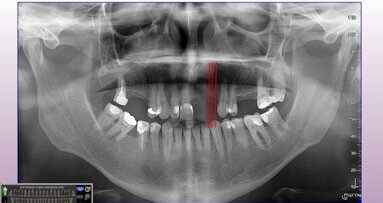

Stomatologia zachowawcza, czyli profilaktyka próchnicy zębów oraz leczenie już powstałych ubytków, to codzienność każdego lekarza dentysty. Najnowsze rozwiązania technologiczne, mogą w znacznym stopniu ułatwić pracę dentystom, a pacjentom uprzyjemnić wizyty lekarskie.

O możliwościach wprowadzenia nowych technologii do stomatologii zachowawczej opowie dr n. med. Maciej Mikołajczych podczas prezentacji pt.: „Stomatologia zachowawcza jeszcze nigdy nie była tak prosta – rozwiązania KaVo i Kerr”.